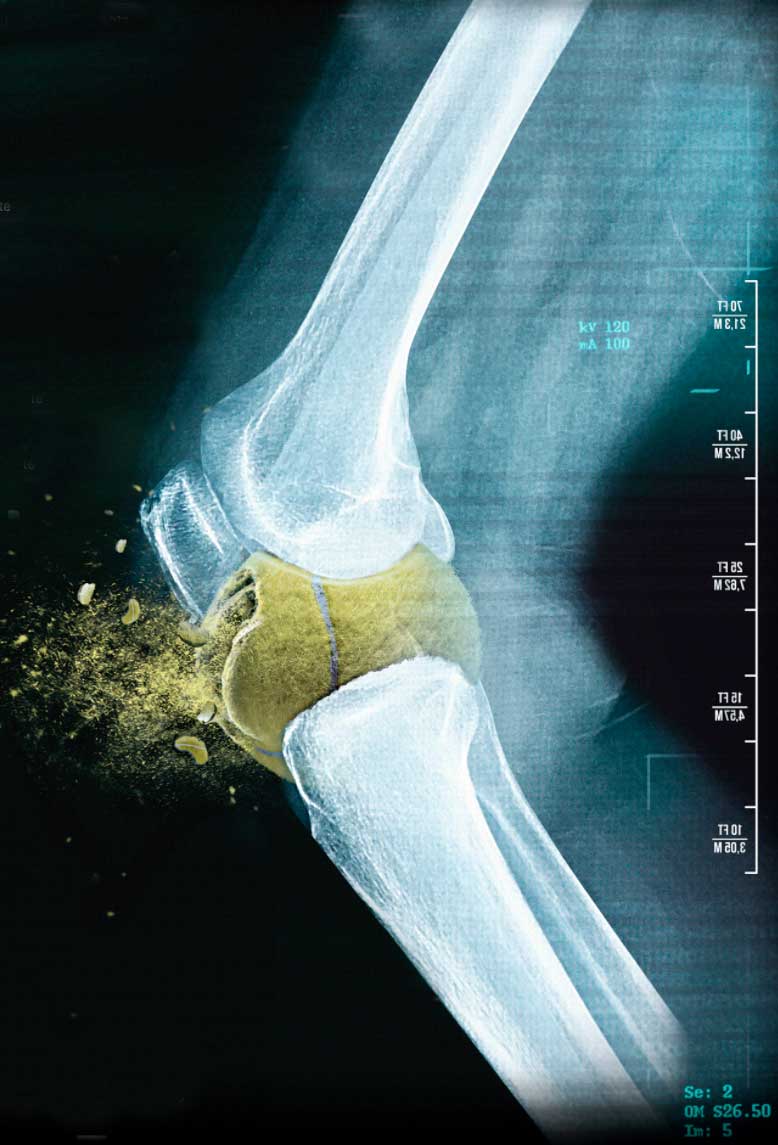

Vasculares, nerviosas, articulares y óseas que se traducen en fracturas conocidas como edema óseo.

Pueden afectar las articulación del cuello, hombros, tórax, pelvis, caderas, muslos, rodillas, piernas, tobillos o el pie, es decir, cualquier estructura del cuerpo está expuesta o tiene el riesgo de sufrir una lesión.